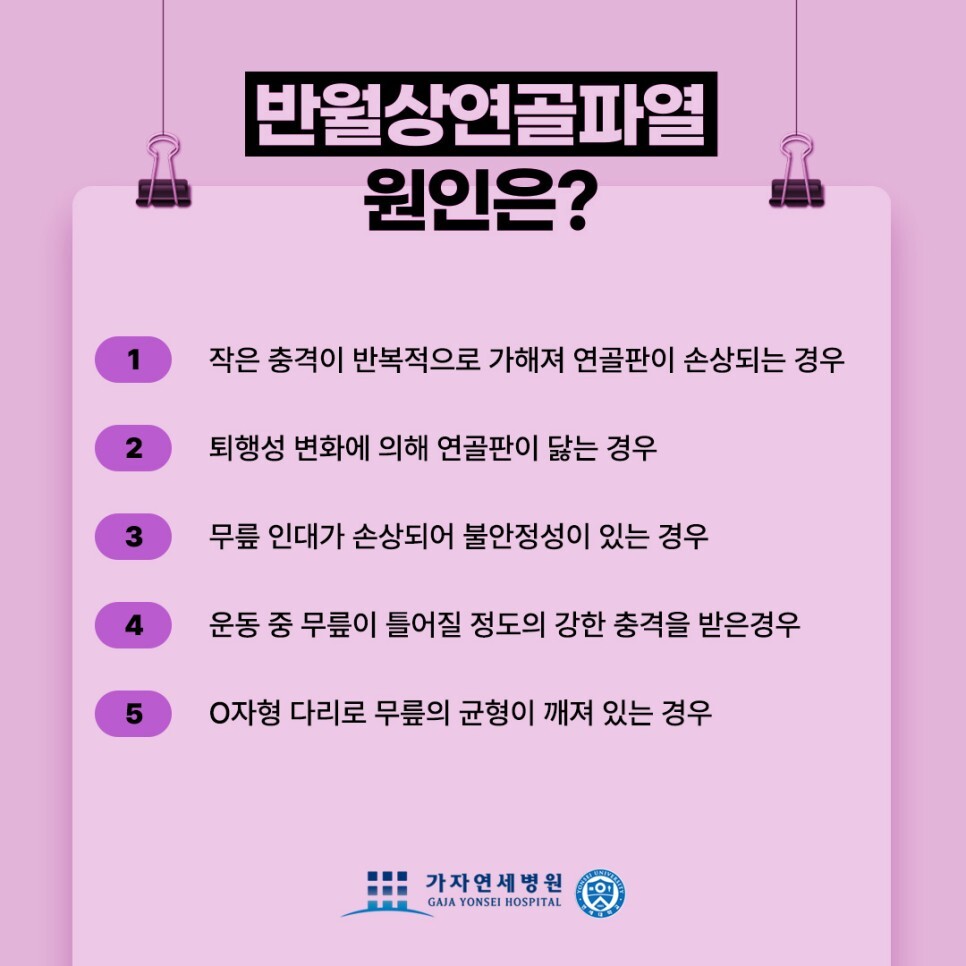

반월상연골파열 발생 원인

젊은 연령층에서 발생하는 반월상연골파열은 대부분 무릎 관절이 비틀리거나 무릎에 많은 양의 회전력이 가해지는 둥 외부의 충격에 의해 파열됩니다. 즉 태클과 같이 직접적으로 접촉이 이루어지는 스포츠, 이를테면 축구, 농구, 핸드볼, 배드민턴 등 방향 전환이 심한 운동을 할 때 파열되는 경우가 많습니다. 그 외에는 교통사고나 낙상사고와 같은 외부의 큰 충격에 의해 파열되는 경우입니다.

중 장년의 연령층인 경우 노화로 인해 무릎 관절이 쇠퇴하게 되면 반월상연골판에 손상을 입을 위험도가 증가합니다. 이러한 경우에는 직접적으로 피해를 입지 않더라도 파열이 발생할 수 있기 때문에 주의가 필요합니다.